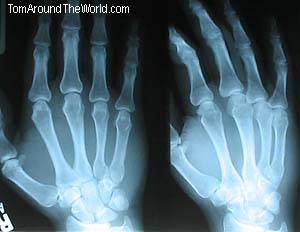

So, at four AM, Kitty and I decided to get dressed and walk up to St. Joseph's Hospital to get my hand looked at. Luckily for me, there weren't many people at the emergency room and we got right in. I explained to the hospital staff that I had a plane to catch in a few hours and needed to get in and out as quickly as possible. Kitty seized my camera and was taking photos as the triage nurse did all the usual blood pressure stuff and asked me what happened. I explained the story to her and she told me I would have to go for X-rays. Within moments I was headed to get pictures of my bones. Upon my return, the nurse took me to look at my X-rays. She informed me that I had broken two bones in my hand. It is commonly known as a "Boxer's Fracture." She pointed out the problems in the picture and I could see the breaks very easily. The bones that broke were the ones behind my ring finger; both the long bone and the small bone that is in the palm of my hand. I asked if I could take photos of my X-rays and was told that I probably couldn't because they were Medical Records. I told the nurse what I do and that people would wonder why I was in a cast for the adventure. I told her that the hospital story was going on my site and I needed to take photos of my X-rays. She started to protest, but I cut her off...

I argued that they were, in fact, MY medical records, and besides, the guys on MTV's "Jackass" show take photos of their X-rays all the time. With that, there were no more questions and I photographed the X-rays.